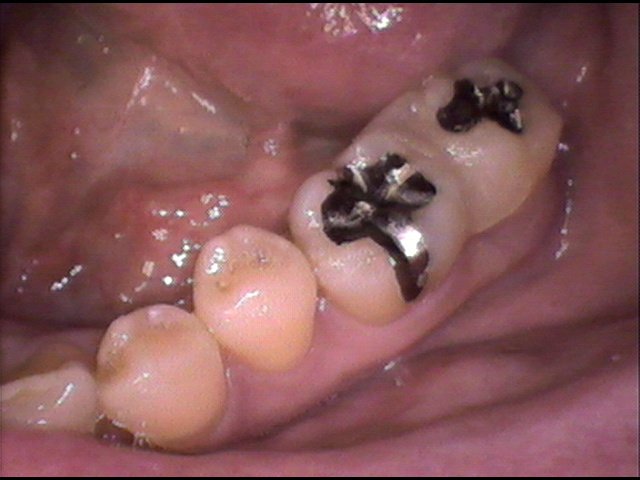

インプラント治療前 60_1

主 訴

下顎奥歯が痛い。腫れている

年 齢

48歳

診療区分

自費